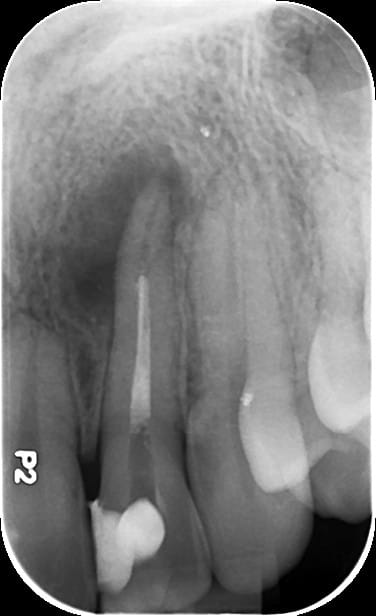

Vous trouverez plus bas une radiographie de ma dent.

Selon mon dentiste, une apectomie n'est pas possible car infection trop importante et la seule solution restante est l'extraction + implant.

Selon lui, il apparait également que l'endo a mal été réalisée par mon précédent dentiste (mais ne veut pas retenter).

Évidemment vu la radio et sans aitre information, le retraitement semble être le traitement de 1ere intention, bien qu'aucun avis certain ne puisse être donné sans examen clinique.

A la radio ça semble pas mal et facile à retraiter, mais on ne voit pas tout à la radio.

La longueur de la 21 ne choque personne ?